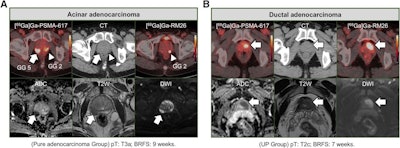

Representative cases. (A) Patient with index lesion (AA) in right peripheral zone, scoring as Prostate Imaging-Reporting and Data System 5 on mpMRI (arrows). Two MRI readers reported discordant findings regarding lesion’s stage (1 T3a and 1 T2a). In contrast, 2 PET/CT readers correctly identified intensely PSMA-positive grade group 5 lesion, with activity extending outside gland contour, indicating EPE (miT3a). Additionally, PET/CT readers correctly identified PSMA- and GRPR-positive grade group 2 lesion (arrowheads) in contralateral site (BID on PSMA-PET/CT), which was not noted by MRI readers. (B) Patient with index lesion (ductal adenocarcinoma) in the transition zone, scoring as Prostate Imaging-Reporting and Data System 5 with bilateral involvement (BID) on mpMRI (arrows). Two MRI readers correctly identified local stage as T2c. Two PET/CT readers also accurately identified lesion on GRPR-PET/CT but failed to note BID on PSMA imaging, which showed positive nodule confined to left transition zone (miT2a). ADC = apparent diffusion coefficient; DWI = diffusion-weighted image; GG = grade group; T2W = T2-weighted.Representative cases. (A) Patient with index lesion (AA) in right peripheral zone, scoring as Prostate Imaging-Reporting and Data System 5 on mpMRI (arrows). Two MRI readers reported discordant findings regarding lesion’s stage (1 T3a and 1 T2a). In contrast, 2 PET/CT readers correctly identified intensely PSMA-positive grade group 5 lesion, with activity extending outside gland contour, indicating EPE (miT3a). Additionally, PET/CT readers correctly identified PSMA- and GRPR-positive grade group 2 lesion (arrowheads) in contralateral site (BID on PSMA-PET/CT), which was not noted by MRI readers. (B) Patient with index lesion (ductal adenocarcinoma) in the transition zone, scoring as Prostate Imaging-Reporting and Data System 5 with bilateral involvement (BID) on mpMRI (arrows). Two MRI readers correctly identified local stage as T2c. Two PET/CT readers also accurately identified lesion on GRPR-PET/CT but failed to note BID on PSMA imaging, which showed positive nodule confined to left transition zone (miT2a). ADC = apparent diffusion coefficient; DWI = diffusion-weighted image; GG = grade group; T2W = T2-weighted. Journal of Nuclear MedicineIn addition, the combined PSMA-PET/CT plus mpMRI analysis further enhanced staging accuracy compared with mpMRI alone (61% vs. 41%, p = 0.002), the researchers reported.